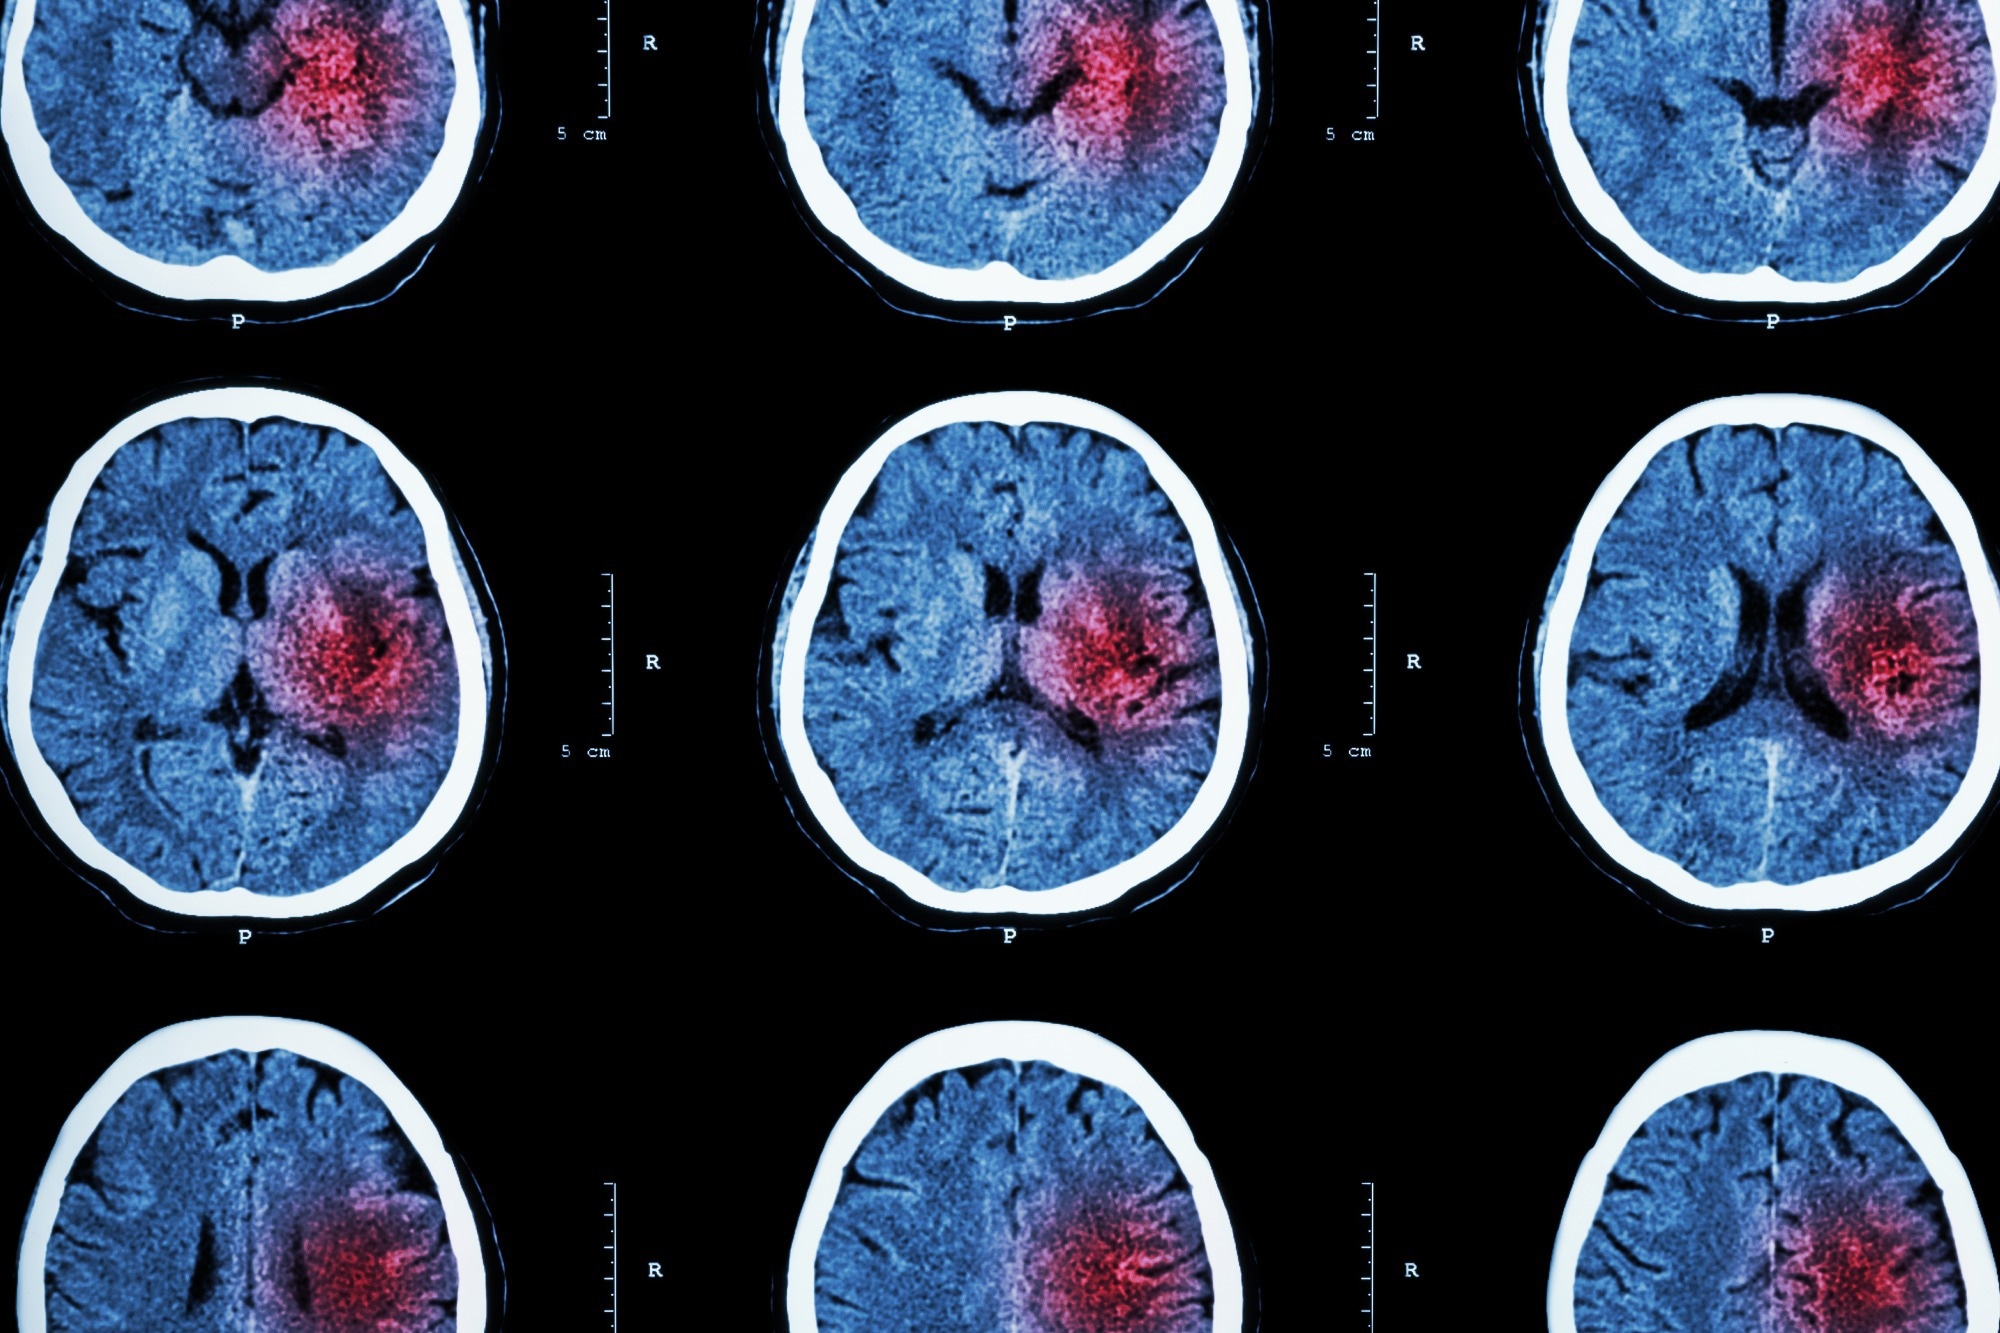

A stroke occurs when a blood vessel that carries oxygen and nutrients to the brain is either blocked by a clot or bursts. Therefore, there are two types of stroke: ischemic and hemorrhagic.

Ischemic strokes – which are the most common and account for 87% of all cases – occur when a blood clot travels to a vessel in the brain and cuts off the blood supply. This prevents brain tissue from getting oxygen and nutrients, and brain cells can begin to die in minutes.

The other type of stroke, hemorrhagic, are often less common than ischemic strokes but can be more severe. These types of strokes are caused by a brain aneurysm burst or rupture of weakened blood vessels.

Image Credit: Inspiring/ShutterstockImage Credit: Inspiring/Shutterstock